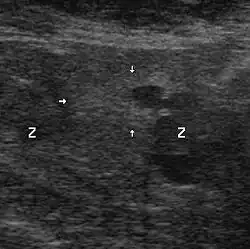

Échographie avec biopsies transrectales

Il n'existe actuellement aucun examen d'imagerie de pratique courante susceptible de détecter seul un foyer d'adénocarcinome prostatique avec une sensibilité et une spécificité satisfaisantes.

Contrairement à une idée encore largement répandue, et bien que cet examen soit ainsi encore souvent prescrit, l'échographie endorectale, seule, n'a pas d'utilité pour le diagnostic positif du cancer de la prostate, au regard du désagrément qu'elle est susceptible d'occasionner. Elle prend, en revanche, tout son intérêt lorsqu'elle sert à guider des biopsies prostatiques. Les autres modalités d'imagerie (scanner, IRM) ont un intérêt dans le bilan d'extension.

Technique

Une sonde d'échographie endorectale munie d'un guide d'aiguille est introduite dans le rectum. Les biopsies sont effectuées avec des aiguilles munies d'un mandrin encoché. Le mandrin pénètre le premier. L'aiguille vient le recouvrir, pour trancher et emprisonner ainsi le fragment de prostate situé dans l'encoche. Les mouvements du mandrin et de l'aiguille sont automatisés par un système de ressorts et le prélèvement est effectué en quelques centièmes de seconde. L'écran de l'échographe, muni d'un repère représentant le trajet de l'aiguille, permet, ainsi, des tirs biopsiques très précis.

Le nombre des biopsies, et l’endroit où elles doivent se faire, ne sont pas bien codifiés et de nombreux protocoles ont été proposés : le but est d'obtenir un échantillonnage aussi représentatif que possible. Actuellement, il est fréquemment réalisé 5 à 6 prélèvements par lobe, soit 10 à 12 au total. Ces nombres peuvent être diminués ou augmentés en fonction de la taille de la prostate, de la tolérance du patient, ou bien s'il s'agit d'une deuxième série de biopsies.